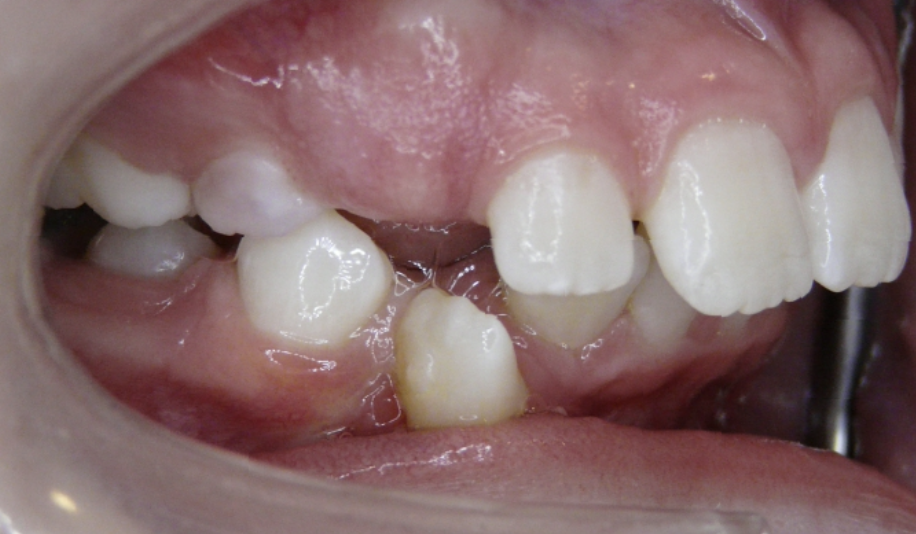

Crowding

Lack of space causes crowding as teeth erupt.